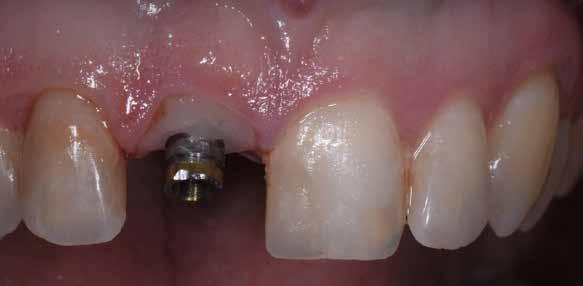

A korai harmicas éveiben járó hölgy rendelőnkbe érkezésének oka a jobb felső nagymetsző fog bizonytalan érzkenysége, elmondása alapján gyermekkorában trauma érte a felső frontrégiót. A frakturált klinikai koronákat kompozittöméssel helyreállították, egyéb kezelést akkor nem tartottak szükségesnek. Az utóbbi hónapokban tapasztalt érzékenység miatt kereste fel rendelőnket. A klinikai vizsgálat (1. és 2. kép) és a CBCT felvétel (3. kép) alapján diagnosztizált külső gyökérreszorpció megoldására a fog eltávolítását, implantátum

bukkális 1. kép: Kiindulási állapot, 2020. január. 3. kép: Kiindulási CBCT felvétel. 2. kép: Kiindulási állapot a palatinális oldal felől.

A behelyeztt implantátum primer stabilitását megfelelőnek ítéltük (kb. 40 Ncm) az azonnali terheléshez (9. kép).

Az extrakciót megelőző szituációs lenyomat alapján gyári, titán, ideiglenes abutment felhasználásával, a szék mellett készített, csavaros rögzítésű, azonnali akrilát ideiglenes koronával láttuk el, melyet 20 Ncm nyomatékkal rögzítettünk (10. kép). Az azonnali terhelés szabályainak megfelelően, az ideiglenes korona nem volt kontaktusban a szomszédos és az antagonista fogakkal.

6. kép: Implantátum-ágy preparáció. 7. a–b. képek: Implantátum behelyezés. 8. kép: A behelyezett implantátum. 10. a–b képek: Azonnali ideiglenes korona készítése. 9. kép: Megfelelő primer stabilitás.

10. c–d képek: A kész ideiglenes korona. 11. kép: A 6 hónapos kontroll felvétele.

A 2020 januárjában elkezdett kezeléssorozat befejezését az év márciusában, hazánkba is begyűrűző Covid-19 pandémia késleltette, így kb. 6 hónap gyógyulás után láttunk hozzá az emergencia profil és a gingivális zenit ideiglenes koronával történő formázásához (11. és 12. kép). A 3 hetente végzett apró alakításokkal sikerült megfelelő ínyprofilt kialakítani, a „rózsaszín esztétika” a páciens számára is megfelelő volt. A bal felső nagymetsző fog meziális kompozit tömés cseréjét követően, individualizált nyitott kanalas lenyomati fejet készítettünk: az akrilát ideiglenes korona profilját átlátszó szilikonnal lemásoltuk, majd a körszimmetrikus gyári lenyomati fej és az ideiglenes korona kontúrja közötti hézagot folyékony kompozittal töltöttük ki (13. kép). Az így készített egyéni lenyomati fejjel vettünk lenyomatot a végleges, kerámialeplezésű cirkónium-dioxid vázas, átmenő csavaros rögzítésű koronához. (A fogtechnikai munkát Nébl Péter fogtechnikusmester készítette.), (14., 15., 16 és 17. képek).

A kész korona átadásakor a páciens elégedett volt az esztétikával, az azóta eltelt évben rendszeres kontrollokon jelent meg, melyek során meggyőződtünk a kemény- és lágyszövetek stabilitásáról (18. és 19. képek).